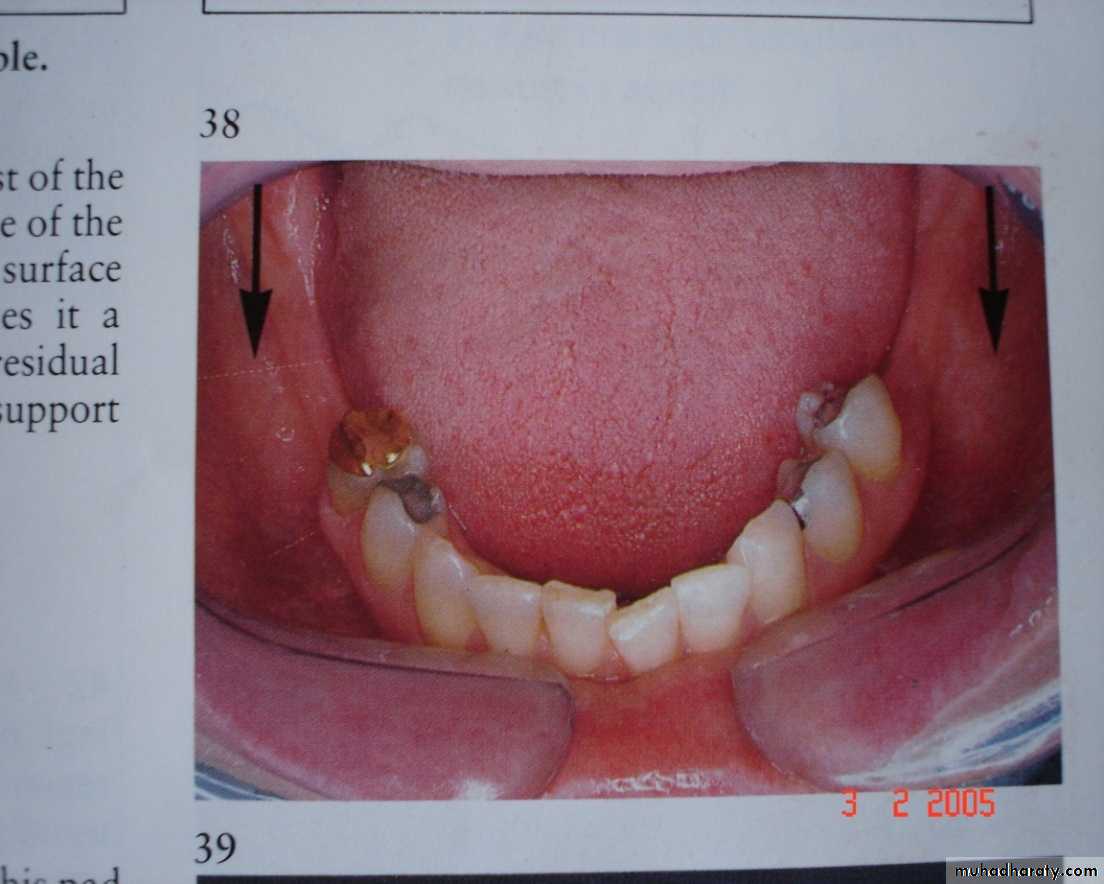

WHERE IS THE PROSTHESIS SUPPORTED.

Tooth supportedTooth - tissue supported:

Sunday, December 18, 2016Dr.Radhwan Himmadi Hasan

39